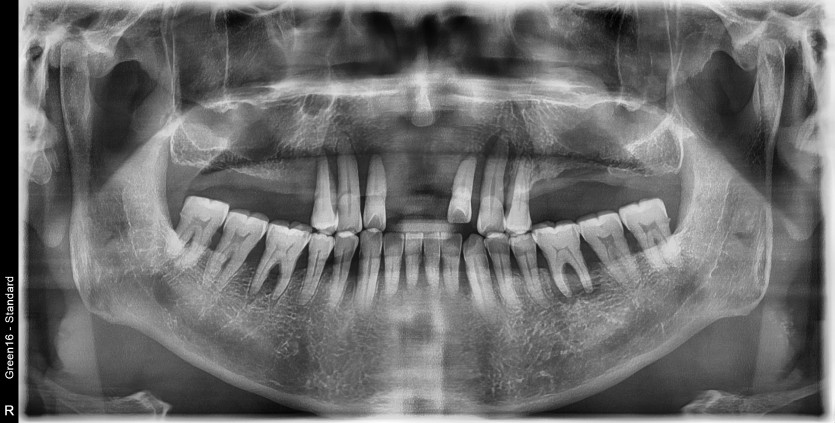

만 68세 상악 전체 임플란트 증례(하악 일부)

상악 전체 임플란트 증례입니다.

(하악 일부)

14개의 임플란트로 완성하였습니다.